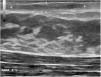

The physical examination revealed an elongated and erythematous indurated area in the area of the areola of the left breast that was painful to touch (Fig. 1). Ultrasound revealed a longitudinal hypoechoic band-like image (15 × 2.4 × 6 mm) in the superficial dermis (Doppler negative) compatible with a fistulous tract (Fig. 2). Based on these findings, the patient was diagnosed with mammillary fistula and prescribed treatment with intralesional triamcinolone, which led to clinical and ultrasound resolution of the lesion. No recurrences were observed during the following 6 months (Fig. 3).